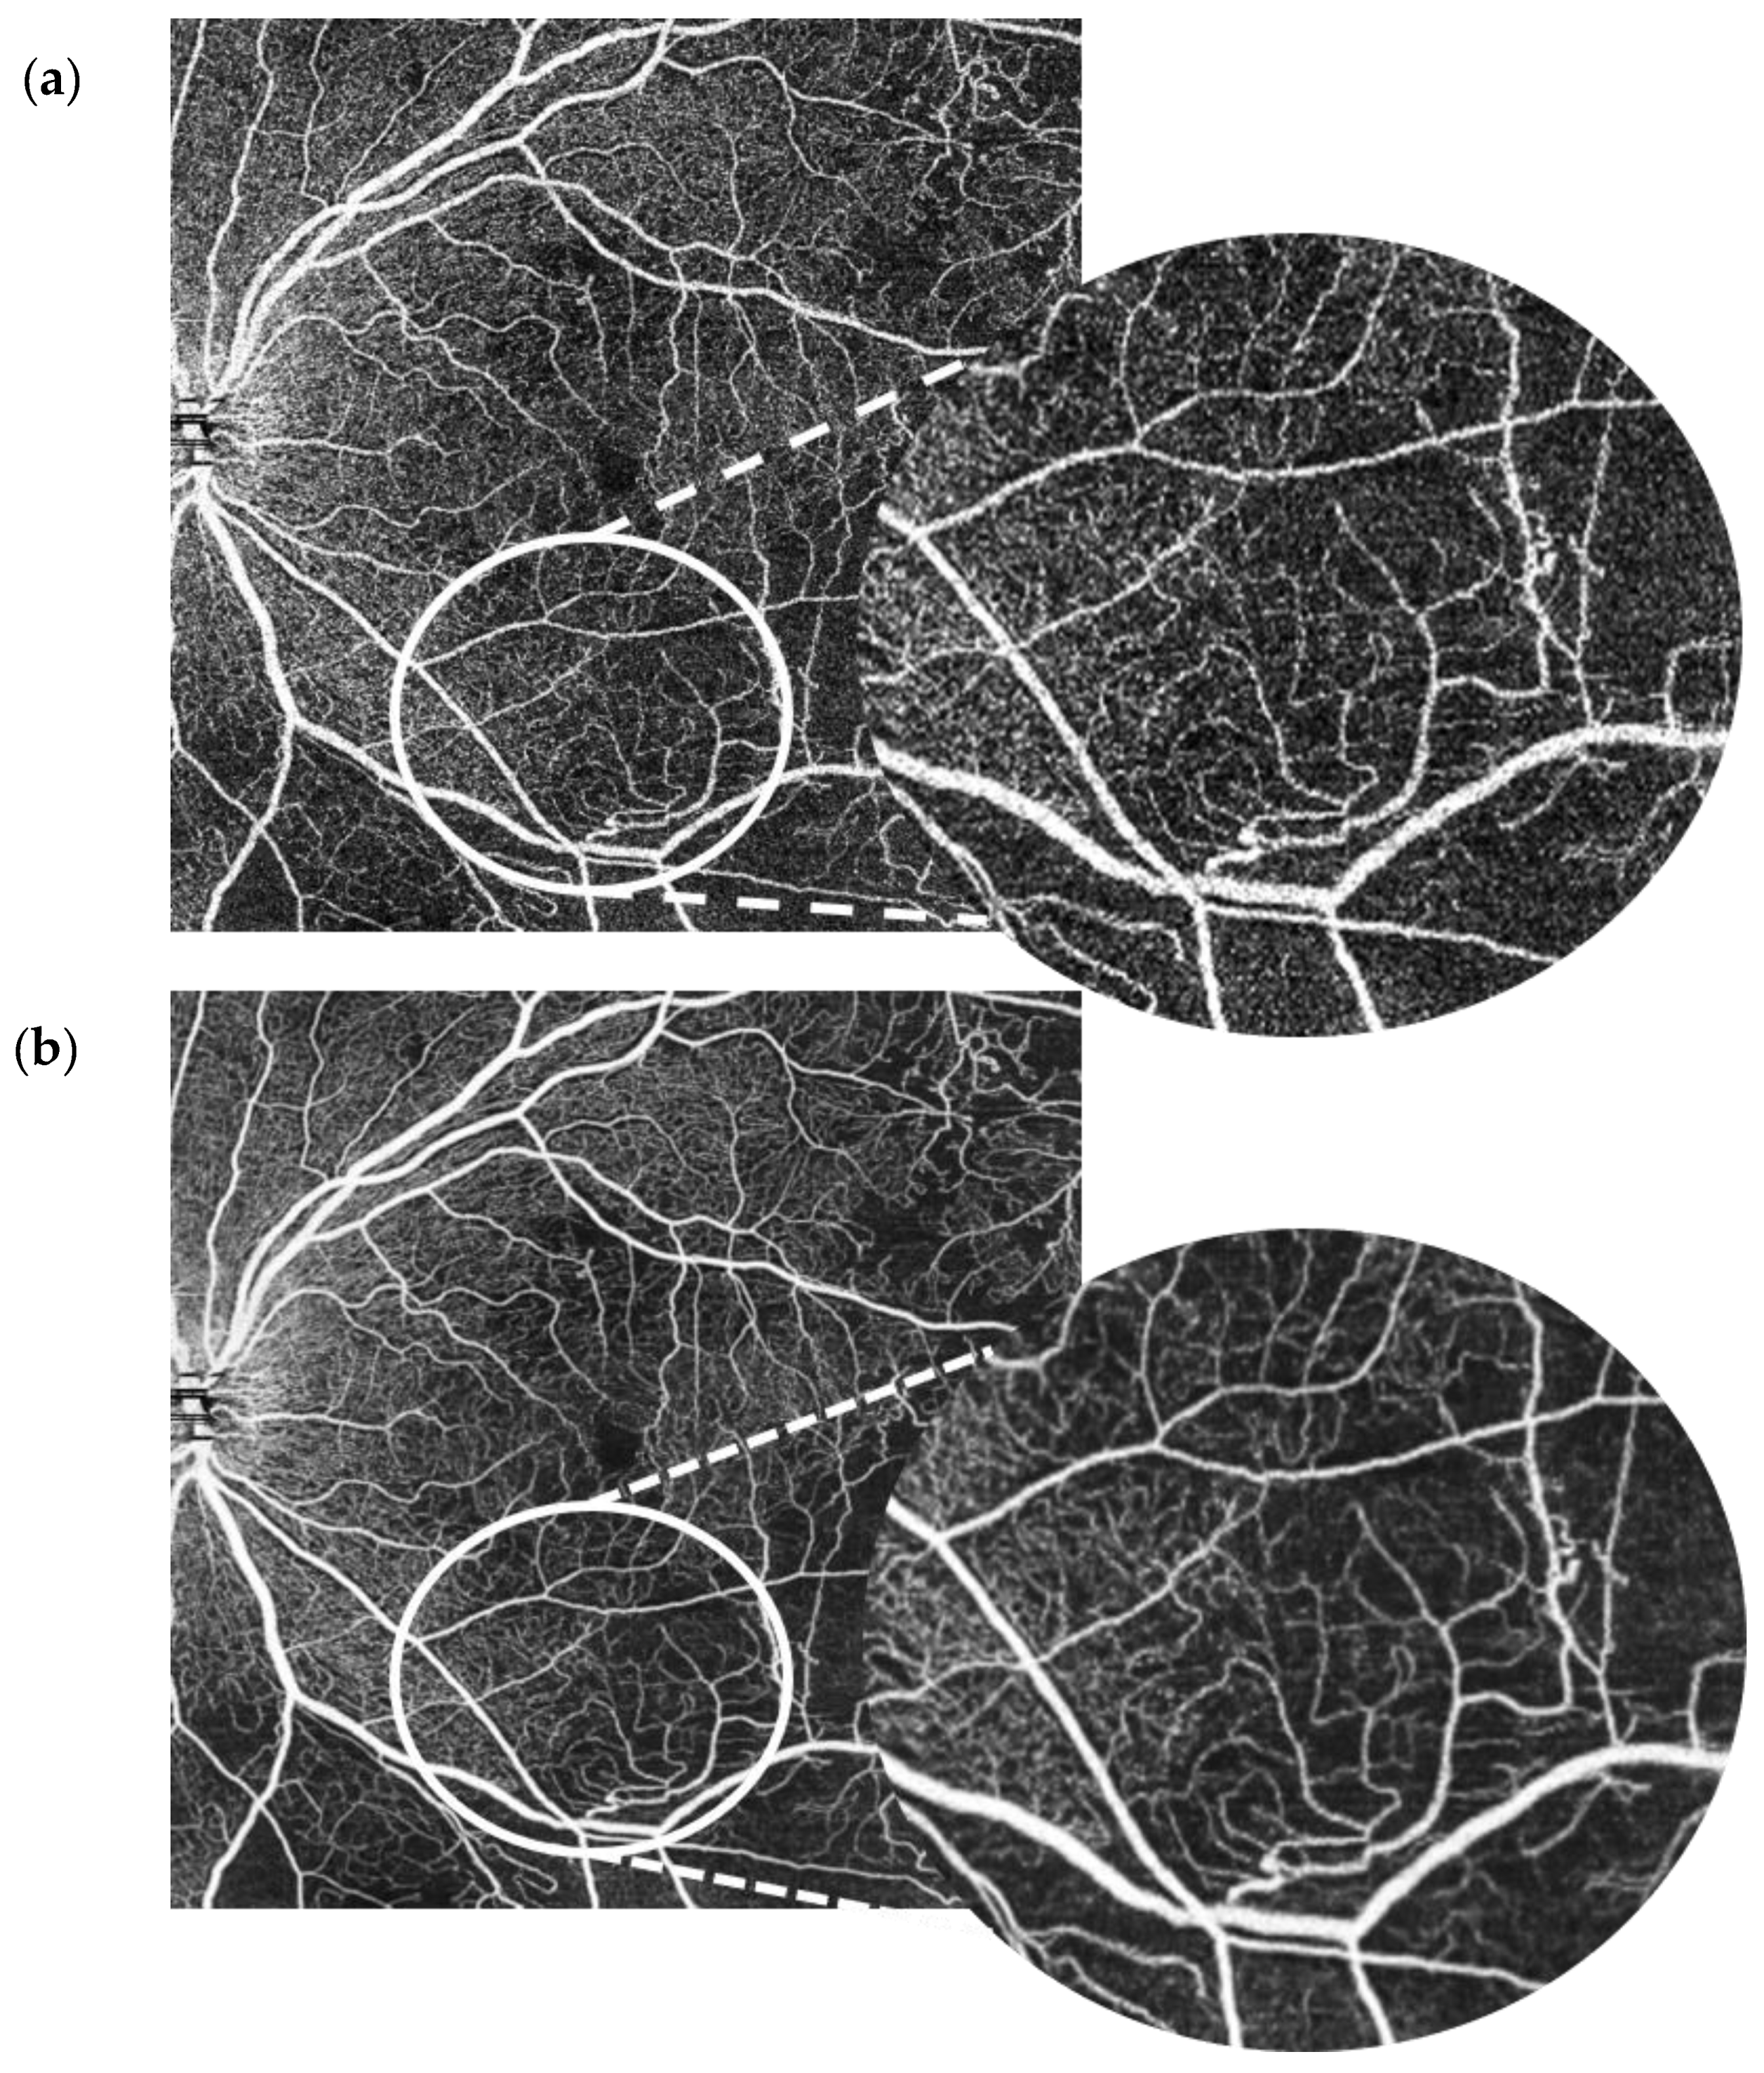

Each patient had wide-field (10 × 10 mm) macula OCT-A scans on the Canon Xephilio OCT-A1 machine with 10-layer automated segmentation and a refresh rate of 70,000 A-scans/second. Depth of field of view was set to 10 × 10 mm with an axial sampling density of 464 × 464 pixels. The number of repetitions was set at 2. The position of the field investigated was centred on the foveal region. En face OCT-As were segmented automatically using built-in software that defines each different retinal layer. The enhanced artificial image was automatically created by selecting the “denoise” button after image acquisition to initiate the algorithm, which completed processing in approximately 2 s. The same technician captured the scans of each patient in this way. All OCT-A images were qualitatively examined for severe motion or shadow artefacts. Figure 1 and Figure 2 demonstrate denoised images created this way along with their corresponding baseline images.

The SCP layer was analysed before and after denoising in 49 scans. Comparison between the original and the denoised image was documented using a proforma as seen in the Appendix A, Figure A2. The denoised DCP of the same 49 scans was similarly analysed and compared with the original image. Please see Figure 2 for an example of an original OCT-A scan of the SCP compared with its denoised equivalent. Please see Figure 3 for an example of an original OCT-A scan of the DCP compared with its denoised equivalent.

Figure 1. 10 × 10 mm OCT-A scan of the superficial capillary plexus in a patient with systemic lupus erythematosus retinopathy. Baseline image (a) vs. denoised image (b).